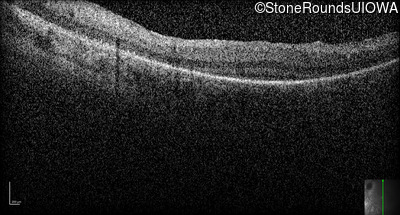

Optical Coherence Tomography - Right -

No Light Perception

Exemplar

Expanded OCT Stack

×